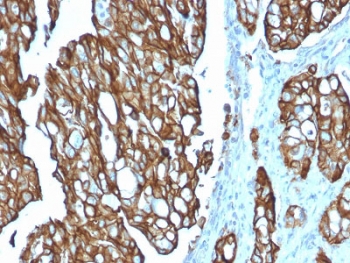

IHC testing of FFPE human colon carcinoma with TROP2 antibody (clone TACSTD2/2151). Required HIER: boil tissue sections in pH 9 10mM Tris with 1mM EDTA for 10-20 min followed by cooling at RT for 20 min.

IHC testing of FFPE human pancreatic carcinoma with TROP2 antibody (clone TACSTD2/2151). Required HIER: boil tissue sections in pH 9 10mM Tris with 1mM EDTA for 10-20 min followed by cooling at RT for 20 min.